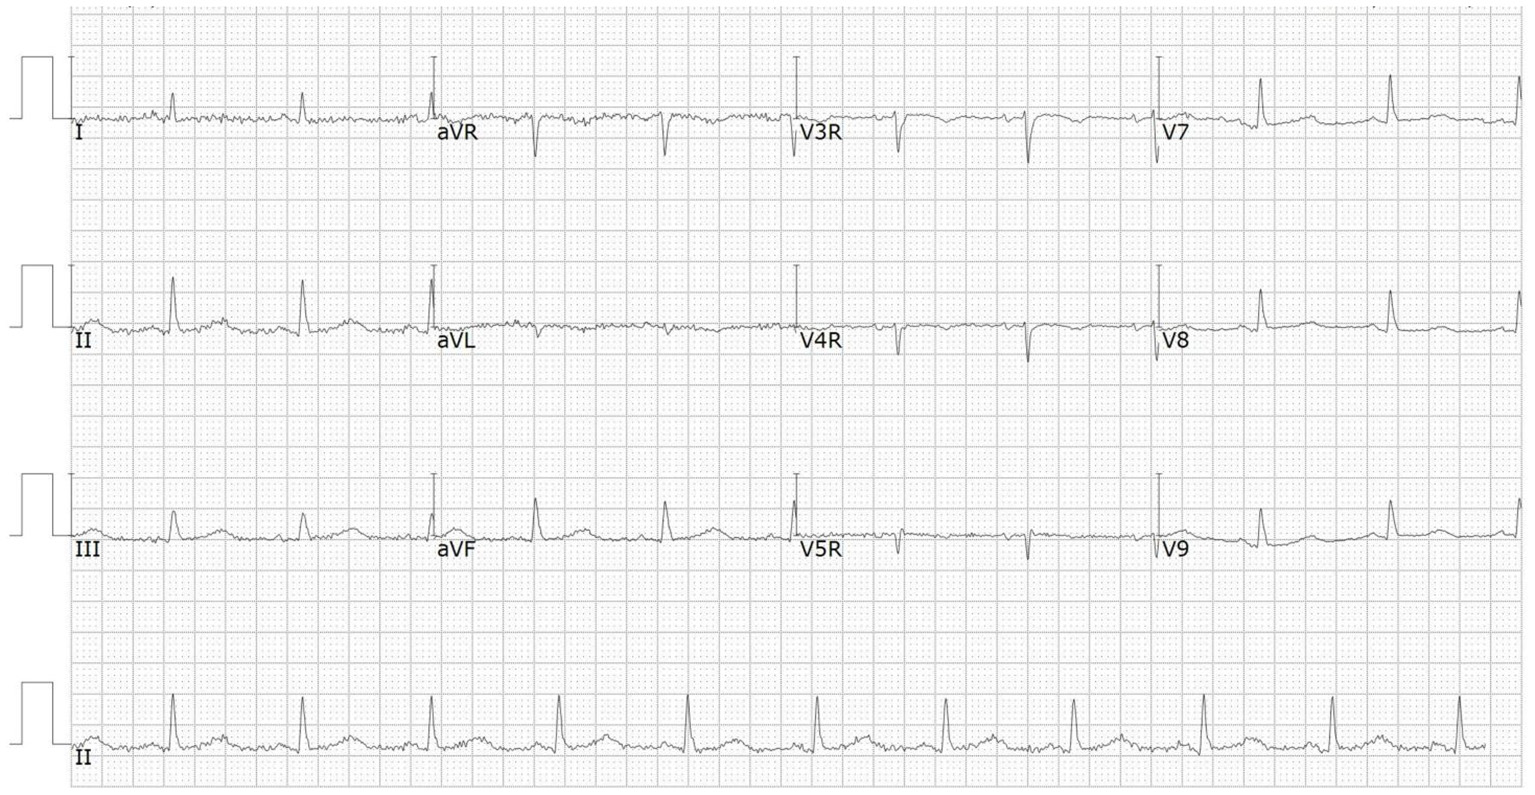

A 66-year-od man with advanced lung adenocarcinoma was admitted to the local chest pain center with progressive chest pain, dyspnea. He had been diagnosed with advanced lung adenocarcinoma 4 month earlier. He had no history of autoimmune or cardiovascular diseases. Cardiac screening tests including cardiac biomarkers, ECG (Figure 1), and echocardiography showed normal results before chemotherapy. The patient was treated with four cycles of albumin paclitaxel plus carboplatin. The CT scan showed that the patient was not responding to chemotherapy. Then he started albumin paclitaxel plus carboplatin for chemotherapy combined with sintilimab (200 mg/injection). 3 weeks after sintilimab initiation, the patient presented with chest pain, shortness of breath and was admitted to the hospital. His vital signs were unstable on arrival (temperature 36.7°C, heart rate, 84 beats/min; respiratory rate 17 breaths/min, blood pressure 84/52 mmHg. The admission ECG showed sinus rhythm with ST-segment elevation in leads V5 through V9 (Figures 2, 3); laboratory test showed that cardiac troponin-I was 9.4 ng/mL (normal range, 0.00–0.03 ng/mL), CK 922IU/L (normal range, 22-270IU/L), CK-MB 109 IU/L (normal range, 2-25 IU/L);NT-proBNP 8290pg/ml (normal range, 0-349pg/ml). Transthoracic echocardiography showed anterior hypokinaesia, severe left ventricular function impairment with a left ventricular ejection fraction of 35%, mild pericardial effusion (Supplementary Videos 4–7). Coronary angiography was performed showing normal coronary arteries (Supplementary Videos 1–3). A diagnosis of sintilimab associated myocarditis was considered. The patient received methylprednisolone (2 mg/kg) and immunoglobulin (0.4g/kg/d) intravenously for 7 days. At day 4, the ECG showed that the elevated ST-segment had fallen back (Figures 4, 5). At day 8, cardiac magnetic resonance was performed and showed late gadolinium enhancement in the mid layer of the septal segment and the subepicardial layer of the inferolateral wall (Figure 6), with an ejection fraction of 47% (Supplementary Video 11). Gradually, the patient's symptoms improved and his vital signs were stable. The lab tests showed persistent decrease of hs-cTnI, myocardial enzyme indexes (Table 1). Echocardiogram revealed improved left ventricular systolic function, with an ejection fraction of 52% (Supplementary Videos 8–10). The dose of glucocorticoid therapy was gradually reduced. The patient was discharged 10 days after admission. He received oral prednisone tablets with gradually decreasing doses and regular follow-up.

Figure 3

ECG on admission showed ST-segment elevation in leads V7 through V9.